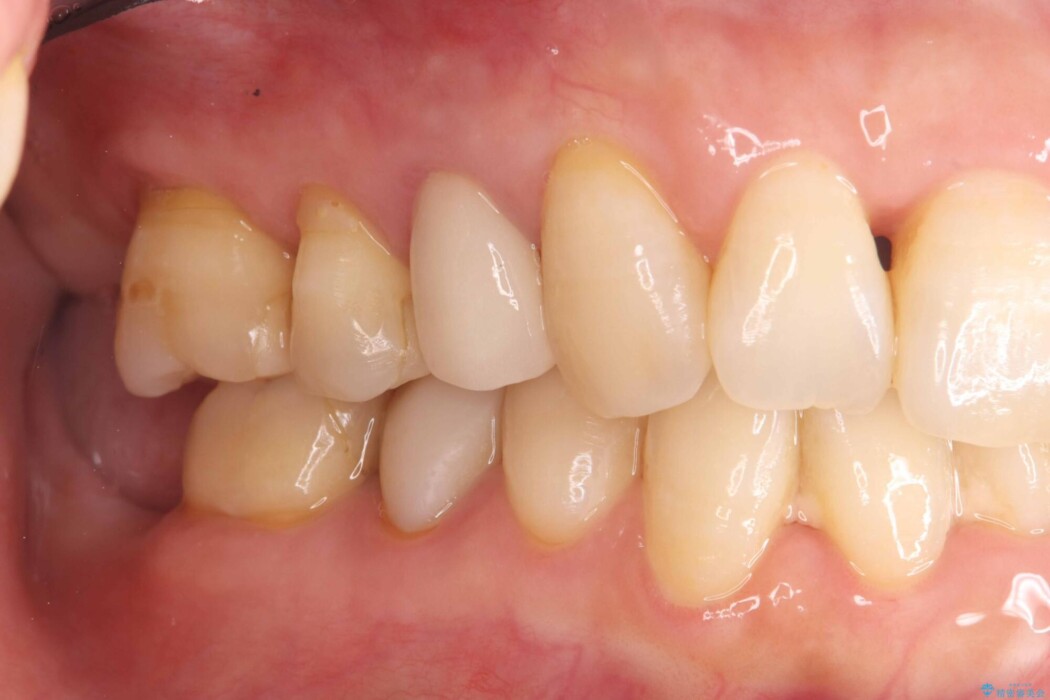

他院で装着されたセラミックインレー(MOD窩洞)が破折したとご来院されました。

再治療にあたり、再度インレーで修復する方法と、歯全体を覆うクラウンによる修復の選択肢をご説明しました。

歯の中央から両側にかけて大きく削られている(MOD窩洞)状態でした。